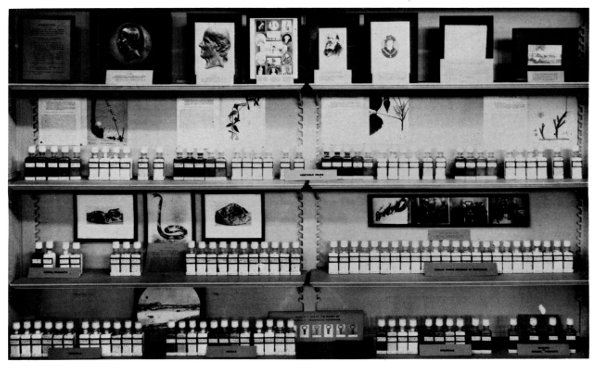

| 43. | History of the Division of Medical Sciences Sami Hamarneh |

269 |